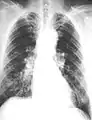

The abnormal chest x-ray and its interpretation remain the most important factors in establishing the presence of pulmonary fibrosis.[11] The findings usually appear as small, irregular parenchymal opacities, primarily in the lung bases. Using the ILO Classification system, "s", "t", and/or "u" opacities predominate. CT or high-resolution CT (HRCT) are more sensitive than plain radiography at detecting pulmonary fibrosis (as well as any underlying pleural changes). More than 50% of people affected with asbestosis develop plaques in the parietal pleura, the space between the chest wall and lungs. Once apparent, the radiographic findings in asbestosis may slowly progress or remain static, even in the absence of further asbestos exposure.[25] Rapid progression suggests an alternative diagnosis.

Asbestosis resembles many other diffuse interstitial lung diseases, including other pneumoconiosis. The differential diagnosis includes idiopathic pulmonary fibrosis (IPF), hypersensitivity pneumonitis, sarcoidosis, and others. The presence of pleural plaques may provide supportive evidence of causation by asbestos. Although lung biopsy is usually not necessary, the presence of asbestos bodies in association with pulmonary fibrosis establishes the diagnosis.[26] Conversely, interstitial pulmonary fibrosis in the absence of asbestos bodies is most likely not asbestosis.[11] Asbestos bodies in the absence of fibrosis indicate exposure, not disease.